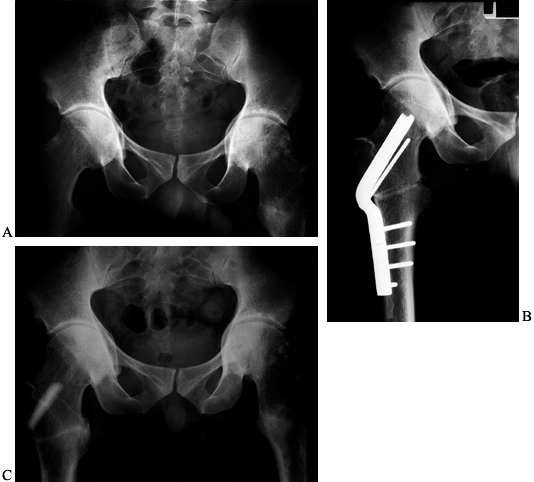

Figure 104.28. Combined varus ITO and PAO. A: AP view of the right hip of a 29-year-old woman with several years of right hip pain. B: Abduction–internal rotation AP view of the right hip prior to surgery. C:

AP view of the right hip following PAO and simultaneous varus–extension ITO. The patient required 4 months of rehabilitation to achieve a normal unassisted gait. D: AP view of her right hip 2 years later, when she had no limp and was playing tennis. |